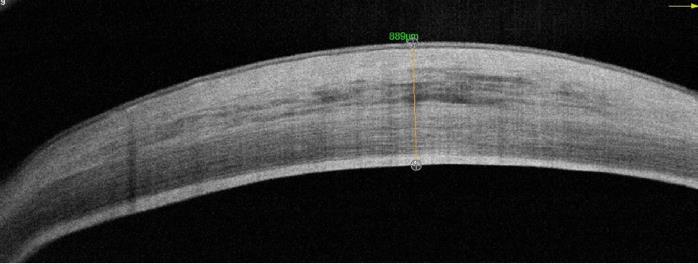

Dr Mimouni presented results of in vivo research with 64 rabbits. One-third received the implant seeded with human corneal endothelial cells, one-third the scaffold alone, and the remainder underwent sham surgery. All underwent unilateral descemetorhexis of the right eye. Subacute (4-week) and chronic (26-week) endpoints were assessed.

“In the sham group that underwent descemetorhexis only, we found severe corneal oedema followed by stromal scarring. In the scaffold-only group we saw that most animals developed subepithelial fibrosis and that there was a 46% detachment rate, with all those animals developing severe oedema. The overall average central corneal thickness was 630 microns. In the PVEK group, at 6 months we saw a 16% detachment rate with a significantly lower average central corneal thickness of 391 microns,” he reported.

• Sham (control 1)

– Severe corneal edema

– Stromal scarring

– Average CCT: 761µm

• Scaffold only (control 2)

– Subepithelial fibrosis

– 6 mo. detachment: 46%

– Average CCT: 630µm

• PVEK

– 6 mo. detachment: 16%

– Average CCT (attached): 391µm

Animal 8046

CCT: 889µm

Animal 8023 CCT: 460µm

Animal 8085 CCT: 386µm